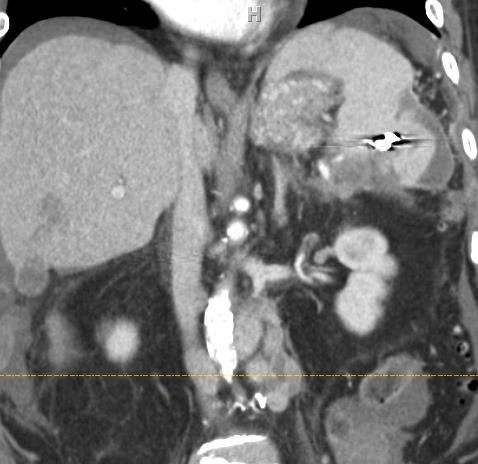

病例:Lower Pole Selection

脾50% 萎缩